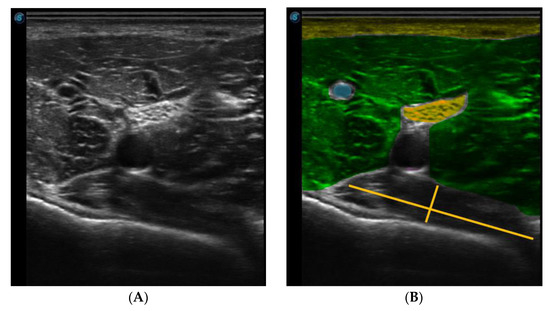

For the ultrasound examination, a linear probe was used and a transverse plane was made, placing the notch of the probe to the patient’s right, as shown in Figure 2.

Figure 2.

Position of the probe in relation to the needle.

The needle was observed in a long axis, so that the entire length of the needle could be seen in the image. Figure 3 shows the ultrasound image of the popliteus muscle, in the deepest part, just below the vasculonervous bundle.

Figure 3.

Ultrasound image of the popliteal region. (A) Ultrasound B-mode image (B) Colored Ultrasound B-mode image (rose-skin, yellow-fat, green-medialis gastrocnemius, blue-vein, magenta-artery, orange-nerve and red-popliteal muscle).